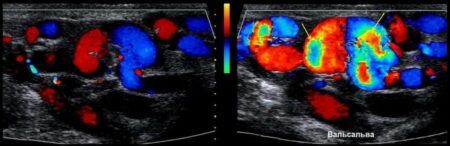

Когда проводится проба вальсальвы при варикоцеле, пациенту предлагают выдохнуть воздух и удерживать дыхание, после чего пациент напрягается, подобно попытке выдохнуть при закрытом рту и носу. Это приводит к увеличению внутрибрюшного давления.

- Положительный — если при проведении обнаруживается увеличение размера варикоцеле или ухудшение кровотока в венах мошонки, это может указывать на более серьезное состояние.

- Отрицательный — отсутствие изменений в размере или кровотоке во время пробы Вальсальвы может свидетельствовать о менее выраженном варикоцеле.